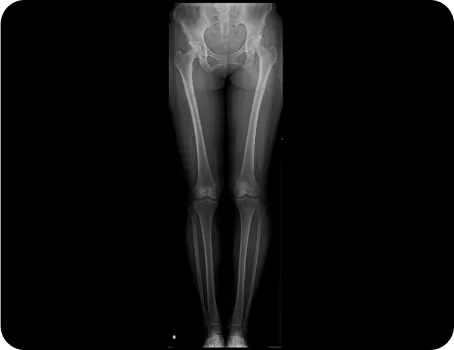

전신체형분석 X-선 검사

풀스파인 촬영으로

신체의 전체적인 문제를 파악하고

통증의 정확한 원인을 찾아

재발을 예방하고, 통증을 개선하는

치료를 합니다.

족압 검사

동적 검사

다리 길이 검사

머리부터 발끝까지 완벽하게 체형을 분석 후 통증을 만들어낸 가해자가 누군지를 찾아내서 치료합니다.